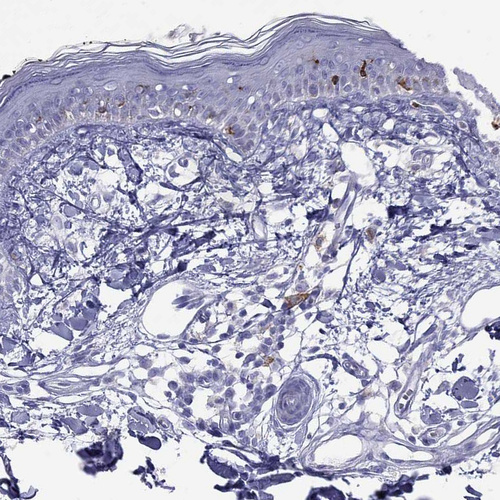

Immunohistochemistry analysis in human skin and pancreas tissues using HPA073187 antibody. Corresponding HLA-DQB2 RNA-seq data are presented for the same tissues.